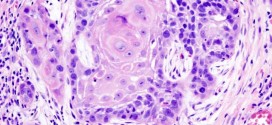

El carcinoma metastásico de la amígdala palatina. La amígdala palatina se desarrolla a partir de la segunda bolsa faríngea, entre el segundo y tercer arcos branquiales. En el tercer mes de la vida intrauterina, el epitelio de revestimiento bucofaríngeo emite prolongaciones (futuras criptas) que se introducen en el tejido mesodérmico. En el cuarto mes, este epitelio forma pequeños brotes, constituidos …